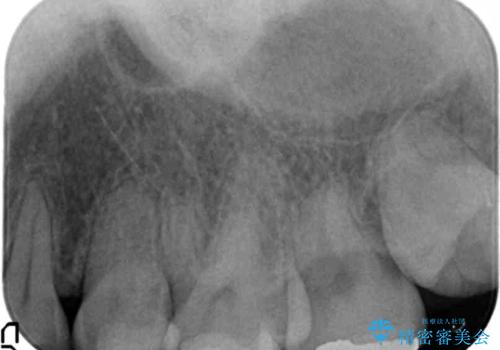

綺麗な仕上がりにご満足下さいました。

奥歯の咬み合わせも良くなったと喜んで頂けました。

患者様の理想とする韓流アイドルの写真を技工士さんに送り、最終的なクラウンの形や色をできるだけ理想に近づけられるよう努めました。

下顎はホワイトニングを行っております。

クラウンの種類:オールセラミッククラウン スタンダード